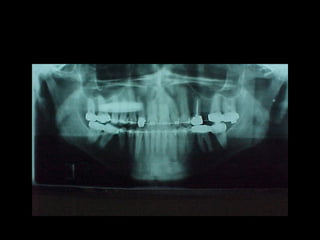

Se observa el número total de órganos dentarios incluyendo

terceros molares.

No hay tratamiento de conductos radiculares

Buen trabeculado óseo de tipo I

Se observa elnúmero total de órganos dentarios incluyendo terceros molares. No hay tratamiento de conductos radiculares Buen trabeculado óseo de tipo I Se observa el número total de órganos dentarios incluyendo terceros molares. No hay tratamiento de conductos radiculares Buen trabeculado óseo de tipo I